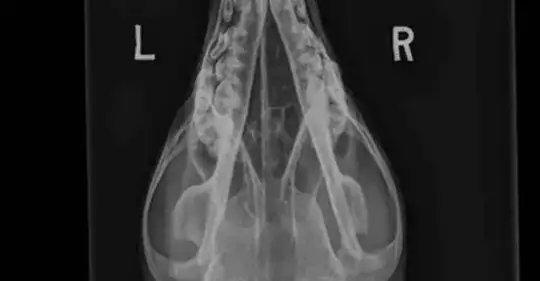

And here's an example of a canine head using the DorsoVentral positioning

and you can see that the image is not reversed which I presume is because this is the normal way to read these type of images.